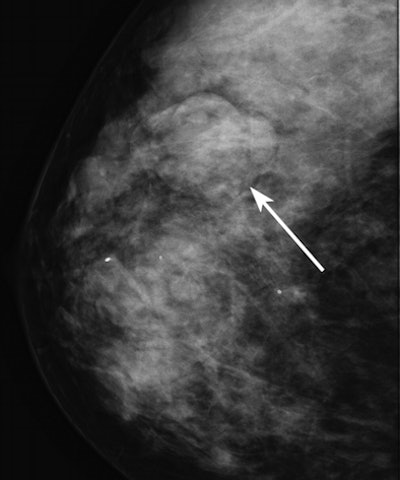

| Mammographic image of an isodense mass (arrow). |